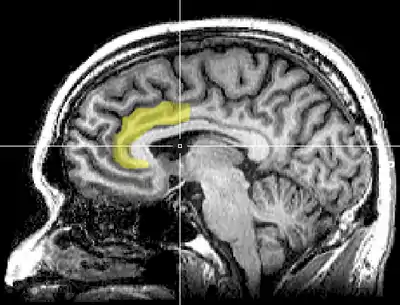

As a relatively new technology, fMRI has only recently been used to assess brain state changes during meditation. Studies have shown heightened activity in the anterior cingulate cortex, frontal cortex, and prefrontal cortex, specifically in the dorsal medial prefrontal area during Vipassana meditation.[8] Similarly, the cingulate cortex and frontal cortex areas were shown to have increased activity during Zen meditation.[9] Both studies comment on the possibility that these findings could indicate some state of heightened voluntary control over attention during mindfulness meditation. Review works by Cahn and Chiesa state that these results indicate consistency in meditation's effect on these regions of the brain, citing a multitude of other studies spanning other meditative disciplines, but mention the need for further investigation with better controls.[5][7]

Brain trait changes have also been observed in neuroimaging studies, most often employing fMRI. In a meta-analysis of 21 neuroimaging studies, eight brain regions were found to be consistently altered, including areas key to meta-awareness (frontopolar cortex/Brodmann area 10), exteroceptive and interoceptive body awareness (sensory cortex and insular cortex), memory consolidation and reconsolidation (hippocampus), self and emotion regulation (anterior cingulate cortex and orbitofrontal cortex), and intra- and interhemispheric communication (superior longitudinal fasciculus; corpus callosum)[14] These changes were distinguished by density increases in grey matter regions and white matter pathways in the brains of individuals who meditate in comparison to individuals who do not. Of all areas with reported findings, a greater number of structural changes were found in the left hemisphere.

There is also evidence to suggest meditation plays a protective role against the natural reduction in grey matter volume associated with aging. One study found evidence that Zen meditators experienced a slower age related decline rate for cerebral gray matter volume in the putamen which plays a role in learning, cognitive flexibility and attentional processing [15] This could suggest a better attentiveness in aging meditators versus non-meditators.